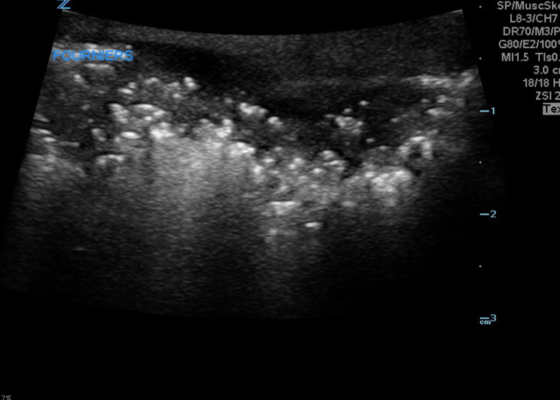

Bedside Ultrasound for the Rapid Diagnosis of Fournier’s Gangrene

DOI: https://doi.org/10.21980/J8CP99Point of care ultrasound (POCUS) utilizing a high-frequency linear probe revealed heterogeneous debris with subcutaneous air within the scrotal wall extending into the perineum consistent with necrotizing fasciitis of the perineum or Fournier’s gangrene (FG). The video shows multiple foci of gas that appear as echogenic dots with “dirty shadows” posteriorly from reverberation artifact arising from gas within the soft tissue.